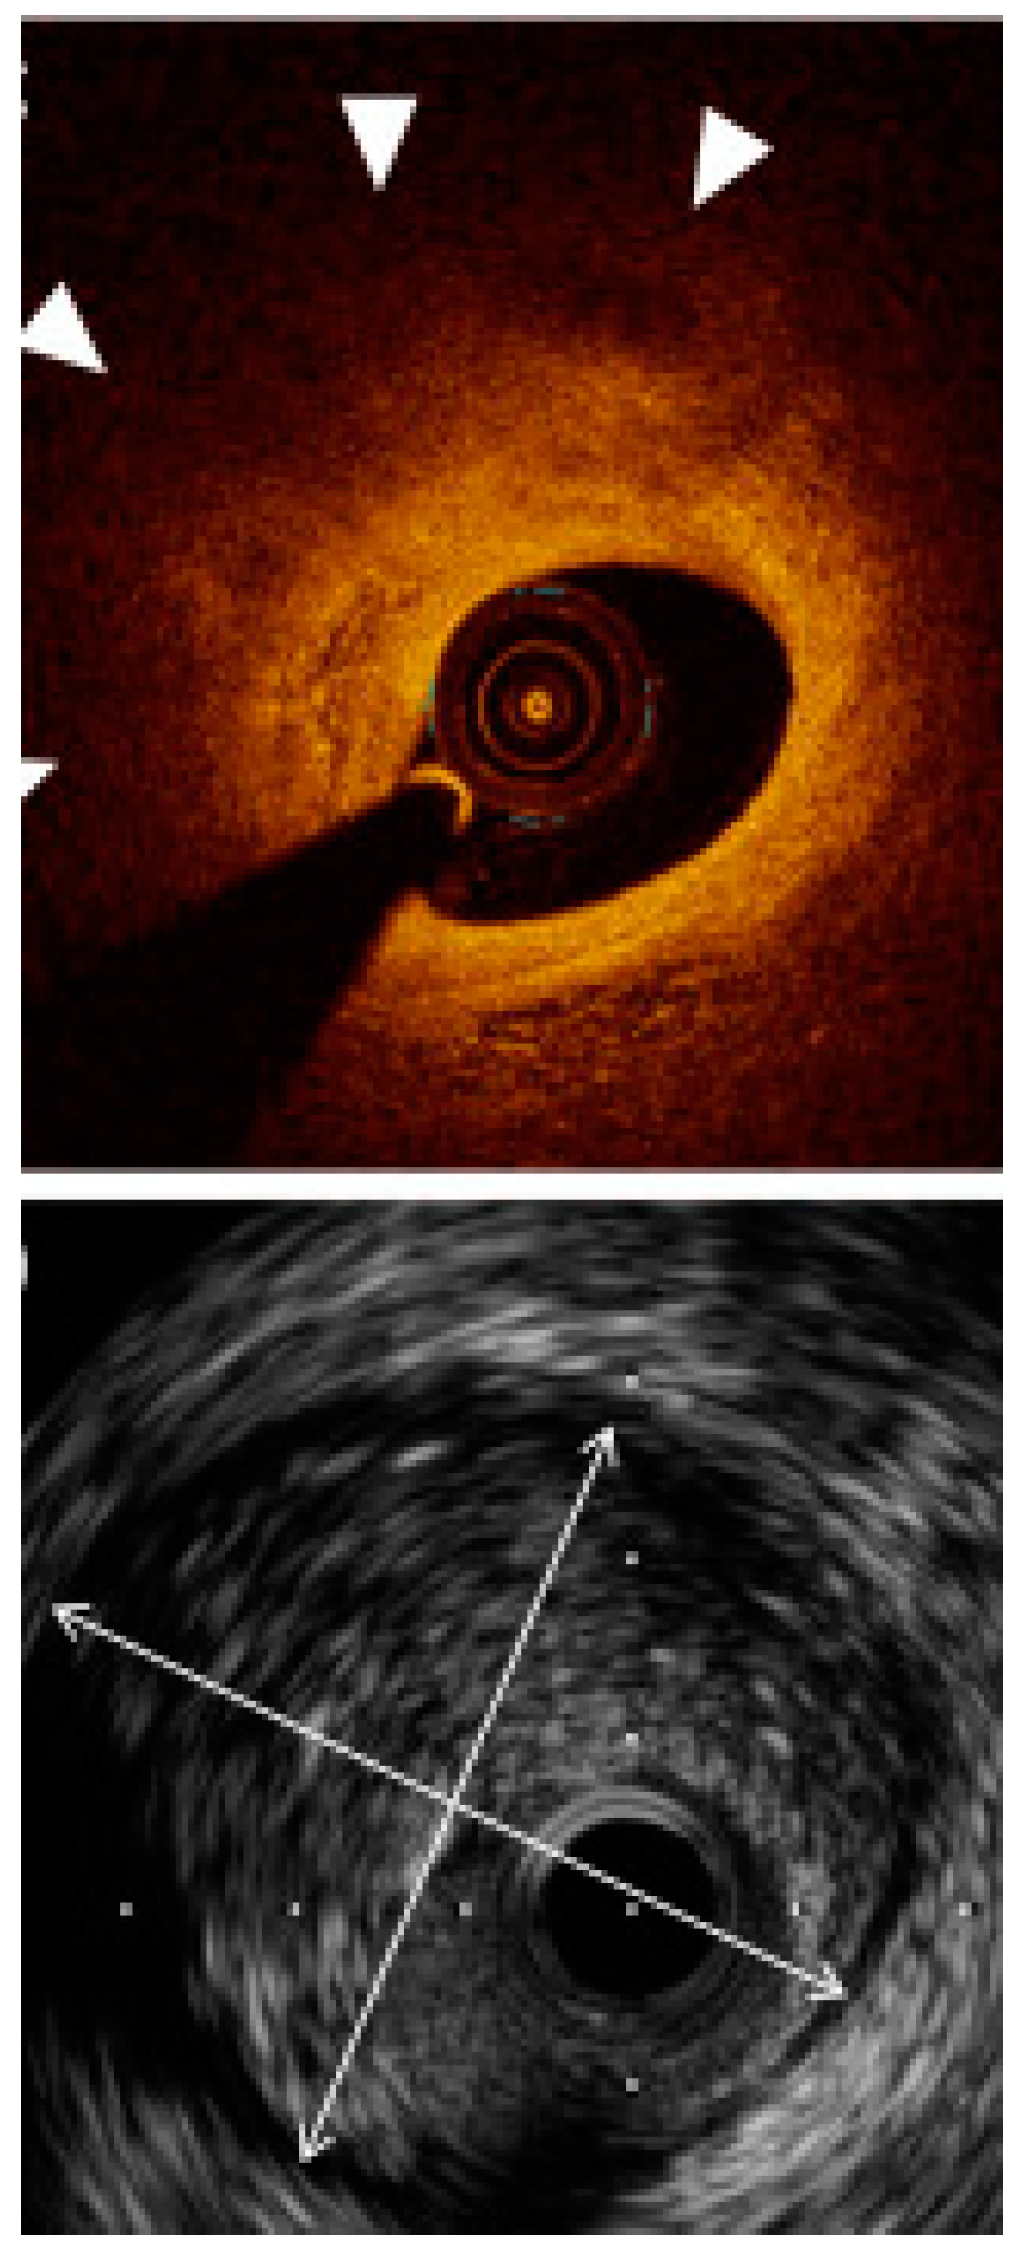

Not only clinical studies but also meta-analyses have demonstrated that both OCT and IVUS improve PCI results, reducing mortality, major adverse cardiovascular events, and the length of the hospitalization [,,]. The benefits seem to be the greatest among the high-risk patients and complex lesions. In clinical practice, physicians should take into consideration the differences between the two methods, mainly higher resolution but lower penetration of OCT and, conversely, lower resolution but higher penetration of IVUS, in order to establish the optimal strategy (Figure 6). The presented studies demonstrate increased applicability in day-to-day practice; presumably, both modalities may be an integral element of routine cardiovascular imaging examinations in the future. All interventionalists should become familiar and regularly trained with the two modalities. Large-scale trials are underway to specifically evaluate the long-term prognostic impact of intravascular imaging use. Moreover, ongoing efforts are made to enhance new alterations of both modalities i.e., high resolution IVUS or OCT 3D reconstructions. Additionally, studies combining OCT and IVUS into a single catheter are in progress. These innovations are undoubtedly expected to bring further marked advancements in this field of cardiology.

Figure 6.

An example of vessel sizing in relation to external elastic lamina (EEL). IVUS (below) was able to show the full EEL diameter (arrow heads), whereas OCT did not visualize the EEL border due to the plaque attenuation and consequently lower signal penetration. Adapted with permission from []. Under Elsevier User license, copyright year 2017.